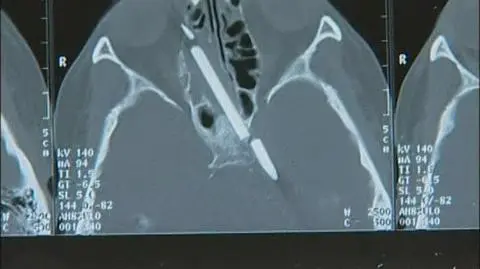

Lekarzom nie udało się usunąć 2 cm ołówka, bo wrósł w tkanki mózgu

Teraz podczas zabiegu z 10-centymetrowego ołówka lekarze usunęli 8 centymetrów. Reszta musiała pozostać nietknięta, bo zrosła się z tkankami. Lekarze zapewniają jednak, że operacja zakończyła się pełnym sukcesem.